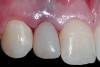

Conversion of the surgical guide to the esthetic provisional was then completed by retrofitting the surgical guide with restorative composite, and then placing the guide back over the provisional copings that were seated on the abutment portion of the one-piece implants, and curing the surgical guide with a curing light (Figure 12). The guide was then reviewed, with the provisionals in the guide, then removal of the provisionals from the vacuform portion of the guide allowed for correction of the marginal portion of the provisionals using a flowable composite material. Shaping the line angles and emergence profile of the provisionals allowed for the proper contours of the provisional to be accomplished (Figure 13). The provisionals were then cemented with a strong temporary cement. The immediate postoperative clinical view can be seen in Figure 14 and Figure 15. The provisionals were immediate, non-functional restorations in centric occlusion and relation, and lateral right and left excursive movements. Figure 16 and Figure 17 show the immediate postoperative radiographic view. Note how the 3-mm diameter implant allows for the adequate space between the root surfaces and the implants placed.

The 3-month postoperative views can be seen in Figure 18 through Figure 20. Note the excellent soft tissue emergence profiles obtained from the properly contoured provisional restorations. After removal of the provisional restorations, further inspection of the contoured emergence profile obtained has been accomplished (Figure 21 and Figure 22). Before impression techniques, transfer copings were seated over the abutment portion of the one-piece implant (Figure 23). A full-arch impression was then taken using medium-body impression material (Take 1 Advanced, Kerr Corporation, Orange, CA) and a regular-body wash material (Take 1 Advanced) to pick up the detail of the emergence profile and impression coping (Figure 24 through Figure 26). After allowing the impression material to set, the impression is then removed from the mouth and inspected (Figure 27). The Take 1 Advanced Medium body has a more rigid set than most other medium materials, so when the coping is placed back in the impression, the possibility of movement during casting is reduced. Please note how the emergence profile obtained has been registered in the impression, and can easily be transferred to the laboratory technician. Laboratory analogues are then placed into the impression coping and forwarded to the laboratory technician for pouring of the casts and final fabrication of the esthetic implant restorations (Figure 28).